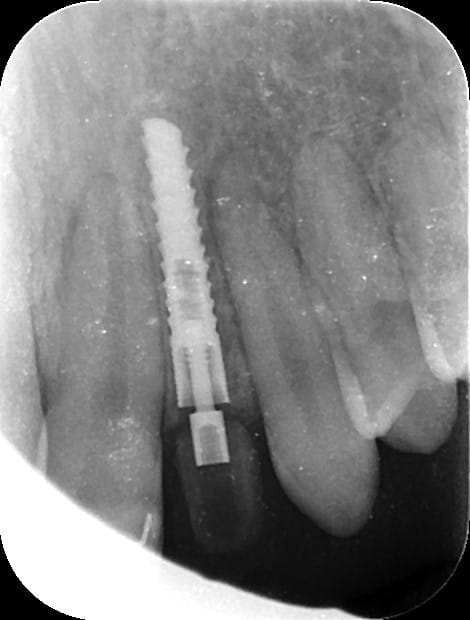

je mets les coupes et les radios post op...

intervention "quasi" flaless, juste des incisions crestales en W pour manager les papilles...

Plc12 hhx60b - Eugenol

Pl12 u0n8gy - Eugenol

Plc22 trdesx - Eugenol

Pl22 on1tll - Eugenol

Pl1222 zuoj0h - Eugenol

12 xdpxmw - Eugenol

22 w4rsbx - Eugenol

très honnêtement c'est bien mais je ne vois absolument pas pourquoi il faut guider l'instrument dans un cas comme ça, car pour la latéralité, tu suis les axes des autres dents, avec précautions ok mais bof, et pour l’épaisseur, c'est un boulevard

j'ai fais ça à main levée, et c'est tout simplement à la porté de tout praticien consciencieux, ce qui n'enlève rien au coté intéressant de ton outil.

c'est un boulevard en épaisseur, ok...

l'intérêt...c'est qu'en une petite heure c'était plié, provisoires inclues...et sans ouvrir grand pour contrôler les proximités radiculaires et faire radio sur radio de contrôle pour ne pas toucher aux racines...

"time is money", et sur cette intervention, au bas mot, c'est une bonne heure de gagnée vs intervention "classique"...